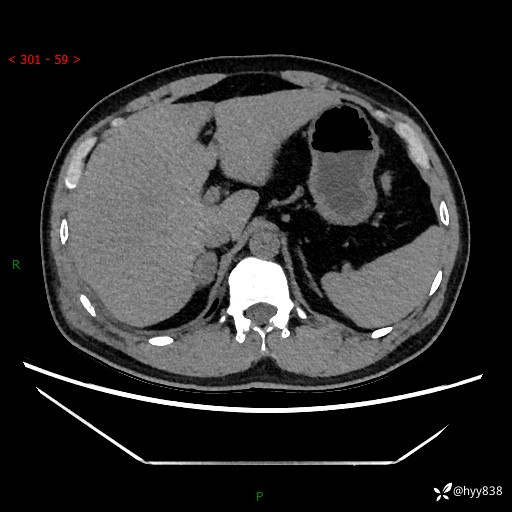

现病史:患者9月4日摔伤在深圳市宝安区中心医院行CT检查提示右侧肾上腺区结节(38*27mm),复查B超提示右侧肾上腺区可见一61*24mm异常低回声团,建议进一步检查。进一步完善增强CT后提示:右侧肾上腺区肿块及周围渗出改变,大致同前,考虑肾上腺腺瘤,不除外瘤内出血可能,否认阵发性头晕、头痛、出汗、乏力等不适,门诊以“ 右侧肾上腺肿瘤”收入住院。 起病来,患者精神、食欲、睡眠可,大便通畅,小便如上述,体力体重无明显改变。

肾上腺CT平扫

增强(动脉期+静脉期)